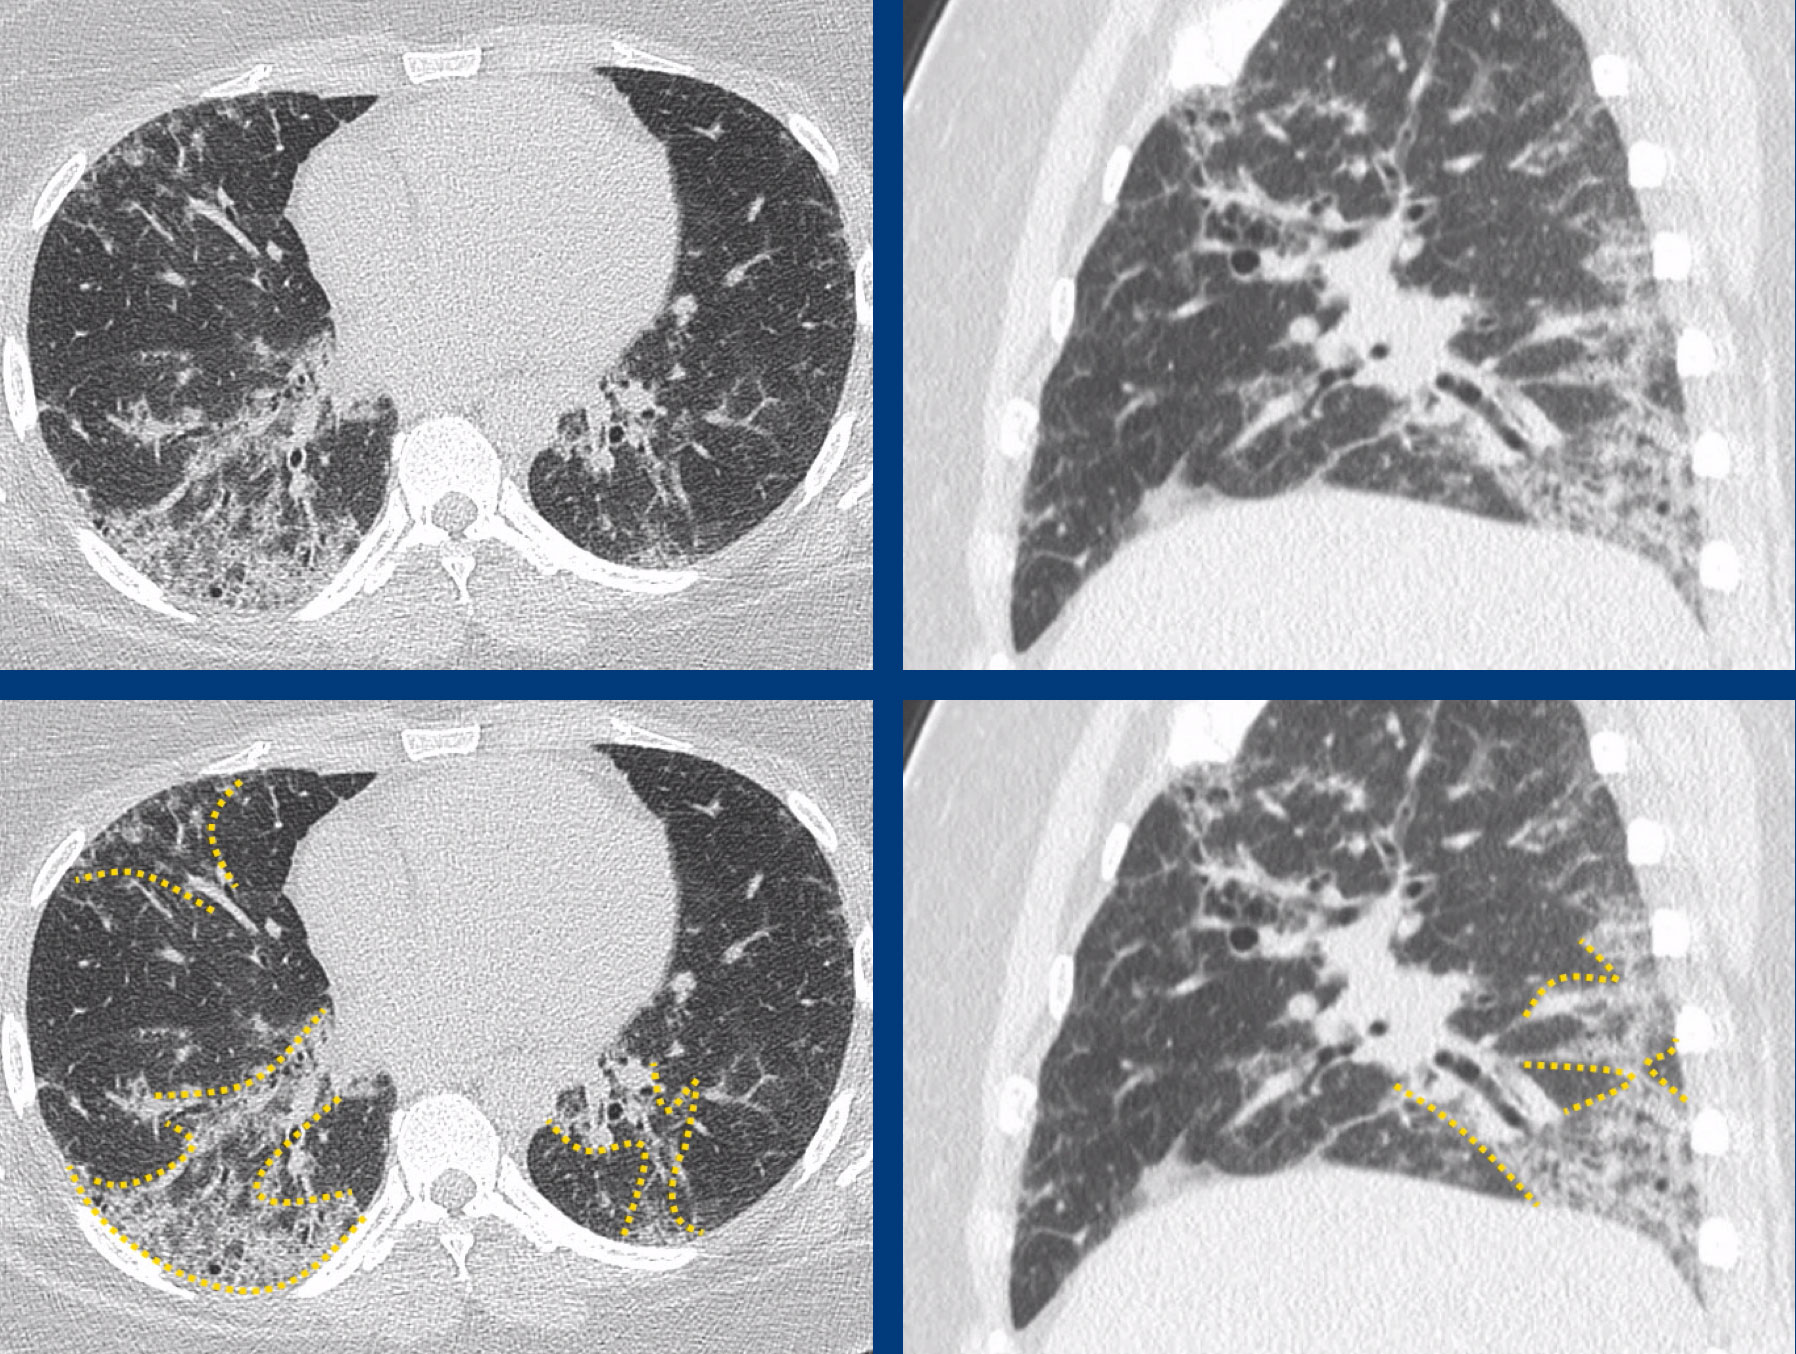

Introducing ILDRADS A Pilot Study of an Interstitial Lung Disease Standardized Reporting Ild Radiology Assistant learn how to identify and differentiate the four patterns of interstitial lung disease (ild) on chest radiographs and ct scans: learn about the causes, symptoms, pathology and radiological features of interstitial lung disease (ild), a group of disorders that affect the. a comprehensive review of the most common interstitial lung diseases and their hrct findings. ila. Ild Radiology Assistant.

The Radiology Assistant Pulmonary Fibrosis Ild Radiology Assistant learn how to identify and differentiate the four patterns of interstitial lung disease (ild) on chest radiographs and ct scans: learn about the causes, symptoms, pathology and radiological features of interstitial lung disease (ild), a group of disorders that affect the. a comprehensive review of the most common interstitial lung diseases and their hrct findings. ila. Ild Radiology Assistant.

The Radiology Assistant Pulmonary Fibrosis Ild Radiology Assistant learn how to identify and differentiate the four patterns of interstitial lung disease (ild) on chest radiographs and ct scans: learn about the various diseases that make up the broader term of interstitial lung disease (ild), and some. ila is a common incidental finding at ct that affects more than 5% of any lung zone and may. Ild Radiology Assistant.